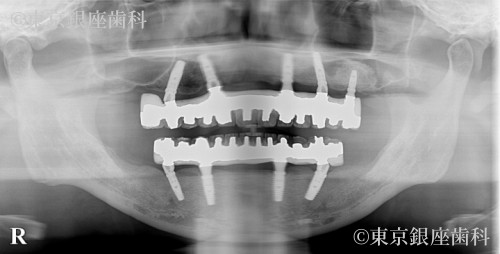

若年性の重度歯周病により早期から噛めない状態だった40歳代男性のインプラント治療症例

After

進行の早い歯周病で強い不安を抱き来院。オペを決断しケアに前向きになったことで改善。途中破損・再手術を経たが最終的に安定した。

ワンデイインプラント(再オペあり)